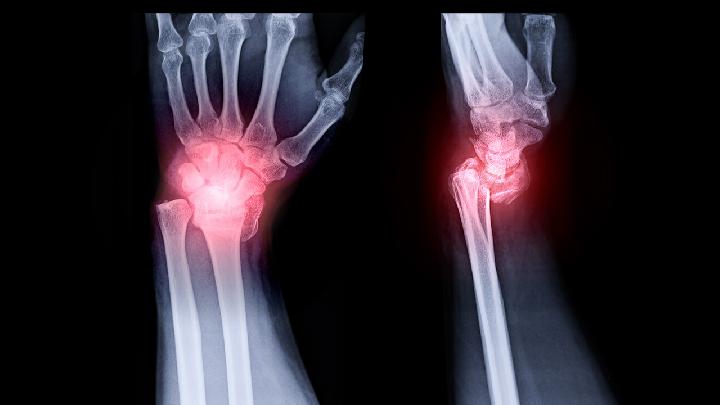

多发性骨髓瘤起病徐缓,早期无明显症状,容易被误诊。MM的临床表现多样,主要有贫血、骨痛、肾功能不全、感染、出血、神经症状、高钙血症、淀粉样变等。

(3)有溶骨性病变